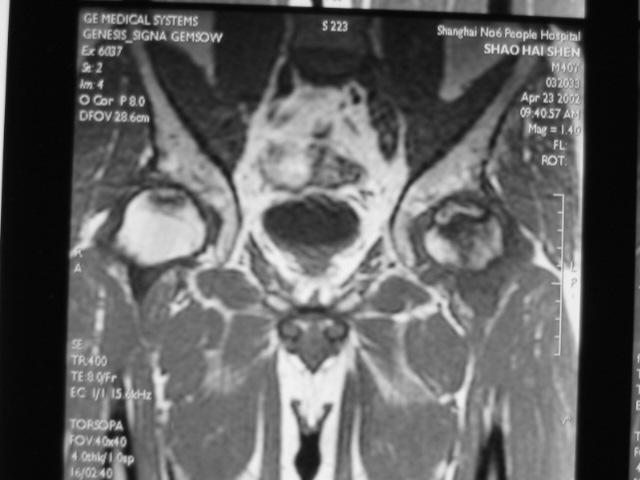

MRI诊断

Ⅰ期

髋关节间隙正常,股骨头光整、不变形。

典型的MRI表现为股骨头前上部负重区在T1W上显示线样低信号区,T2W上显示为局限性信号升高或“双线征”。

在MRI上出现“双线征”,这是股骨头缺血坏死的特异性MRI表现之一。